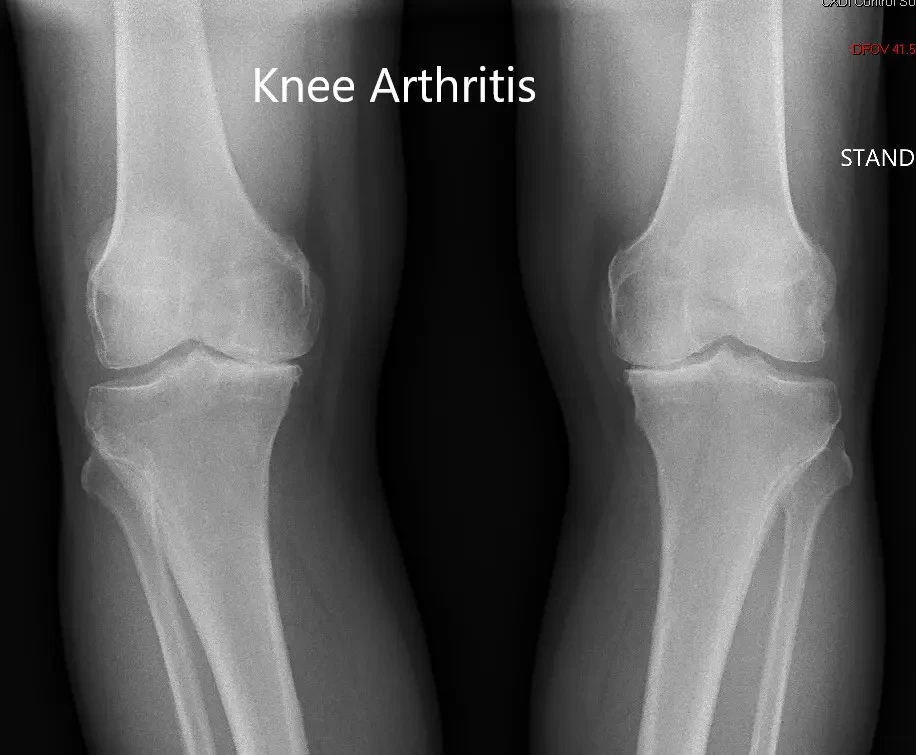

Imaging study revealed severe osteoarthritis of both knees. Considering her lifestyle limiting knee pain, she was offered bilateral custom total knee replacement. Risks, benefits, and alternatives were discussed thoroughly with her and her daughter. She agreed to go ahead with the surgery.

Preoperative X-ray showing the AP view of both the knee joints